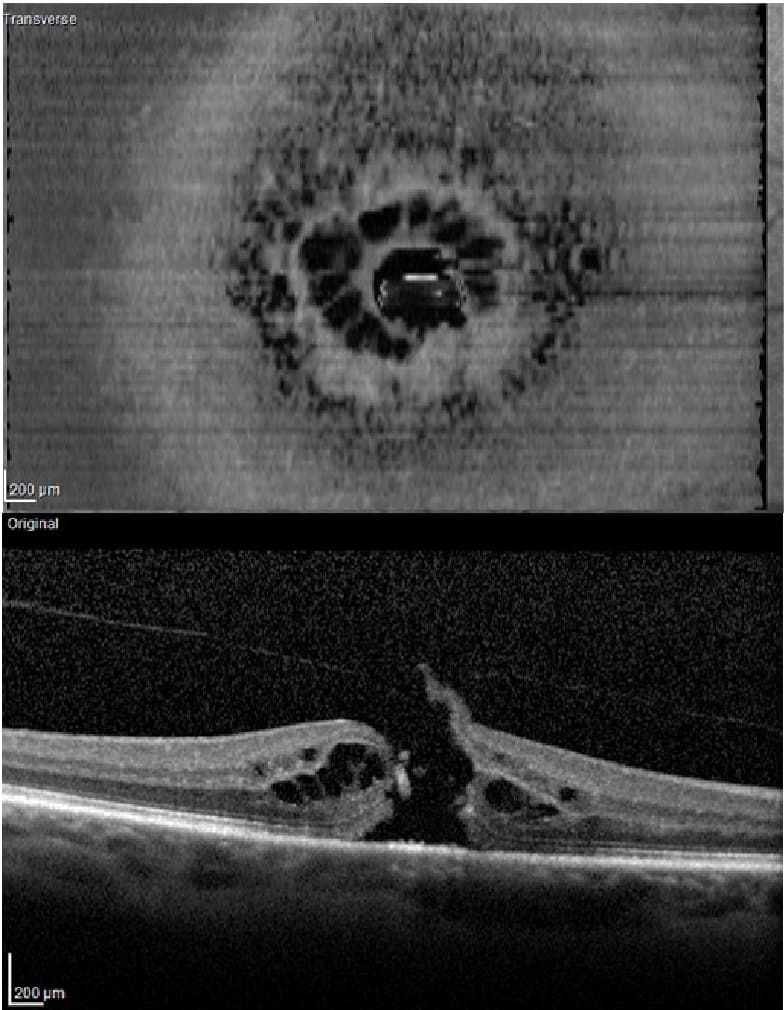

→ Tomografía de Coherencia Óptica u OCT Macular: con esta prueba determinamos el tamaño y la forma del agujero macular para observar el estado de las diferentes capas de la retina y descartar edema macular quístico.

→ Tomografia de coherencia óptica OCT de agujero macular completo.